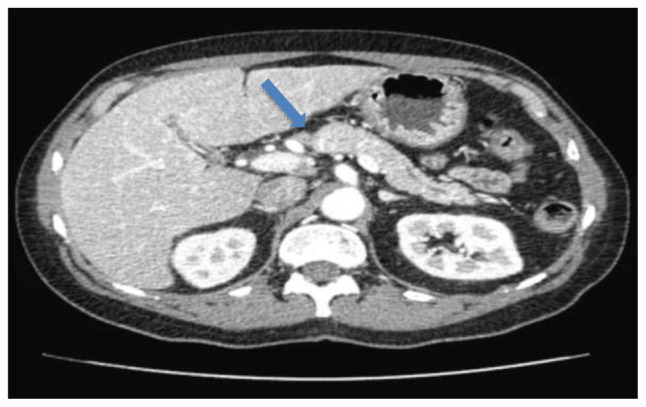

一位67岁男性患者,在过去的三个月里表现为厌食、体重减轻、皮肤肿块和腹部疼痛。影像学显示肺肿块及胰头囊性病变。在最初的诊断检查和临床恶化后,在病理上看到广泛的芽殖,导致播散性芽殖菌病的诊断。患者接受两性霉素B脂质体治疗14天后,再加伊曲康唑治疗,临床表现明显改善。我们回顾了医学文献中所有涉及胃肠道器官的播散性芽孢菌病病例。虽然胰腺受累是罕见的,我们建议应该怀疑那些快速增长的胰腺肿块,即使是免疫功能正常的患者。最后,应迅速进行组织活检,但如果初步结果为阴性且临床怀疑仍然很高,则可能需要重复活检。

A 67-year-old male patient presented with anorexia, weight loss, skin masses, and flank pain over the past three months. Imaging revealed a lung mass and a cystic lesion in the pancreatic head. After initial diagnostic work-up and clinical deterioration, broad based budding, seen on pathology, led to a diagnosis of disseminated blastomycosis. After receiving a 14-day course of liposomal amphotericin B followed by itraconazole, the patient showed significant clinical improvement. We reviewed all disseminated blastomycosis cases in the medical literature involving gastrointestinal organs. Although pancreatic involvement is rare, we suggest that it should be suspected in those with a rapidly growing pancreatic mass even in immunocompetent patients. Finally, tissue biopsy should be obtained expeditiously, but repeat biopsy may be indicated if initial results are negative and clinical suspicion remains high.